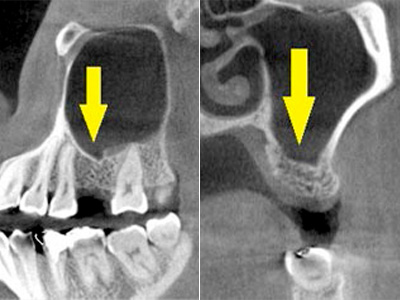

CTで見ると、骨吸収の様子が良く分かり、下顎骨の中を通る神経近くまで骨がありませんでした(黄色矢印)。

さらに、CTで別な方向から見ると、黄色矢印のように骨が吸収されていて、緑色矢印で示される神経の通る管に迫り、インプラントが埋入できるような骨量はありませんでした。